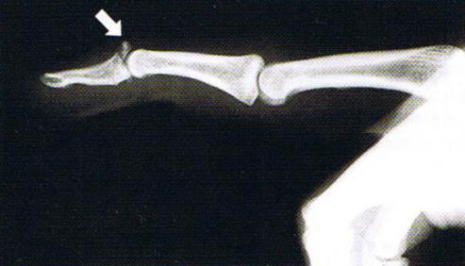

第1関節が曲がった状態で、自分で伸ばすことができず手伝うと伸ばすことができれば診断は容易です。レントゲン写真で骨折の有無を確認します。

マレット変形(槌指) 診断